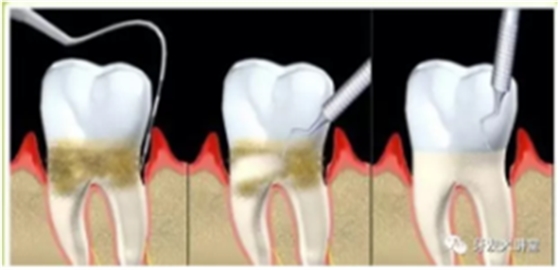

牙周炎,中國成年人后半生永遠的 痛 !

一旦牙結(jié)石達到相當程度,將不可避免地刺激牙齦發(fā)炎,刷牙出血,這時單純依靠刷牙或口服消炎藥已經(jīng)無法去除病因,而偏偏多數(shù)人在這個階段執(zhí)念于“消炎”,失去牙齦炎的最佳干預治療機會,牙齦炎持續(xù)進展,從量變到質(zhì)變,產(chǎn)生牙周袋,牙槽骨吸收,牙齒松動,口臭,即形成牙周炎。

圖為大量齦下結(jié)石刺激導致牙齦廣泛充血腫脹,牙齒松動,局部已形成牙齦瘤,治療上比單純牙周炎復雜。

在治療方案上,首先,全口超聲洗牙(齦上潔治)仍然是基礎治療,但遠遠不夠,更專業(yè)的齦下刮治,深牙周袋的處理和微創(chuàng)手術(shù)比如牙齦翻瓣術(shù),松牙固定術(shù)(臨時或永久固定)等等手術(shù)方式與手術(shù)時機的選擇,牙周炎不同分期的不同處理,因為涉及過于專業(yè),除了牙周??漆t(yī)師以外的其他牙醫(yī)甚至很多都從未涉足此領城,在此不再詳述。